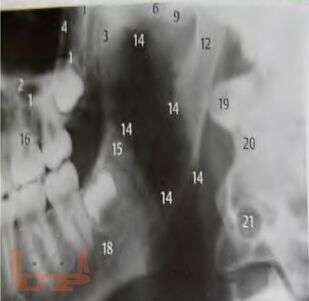

В учебно-методическом пособии представлен доступный алгоритм лучевой диагностики при синдроме болевой дисфункции височно-нижнечелюстного сустава. Алгоритм дает возможность повысить точность диагностики, а следовательно, и эффективность лечения пациентов, индивидуализировать методы терапии каждого больного.

Пособие предназначено для врачей разных специальностей: стоматологов, неврологов и рентгенологов, а также интернов и ординаторов.